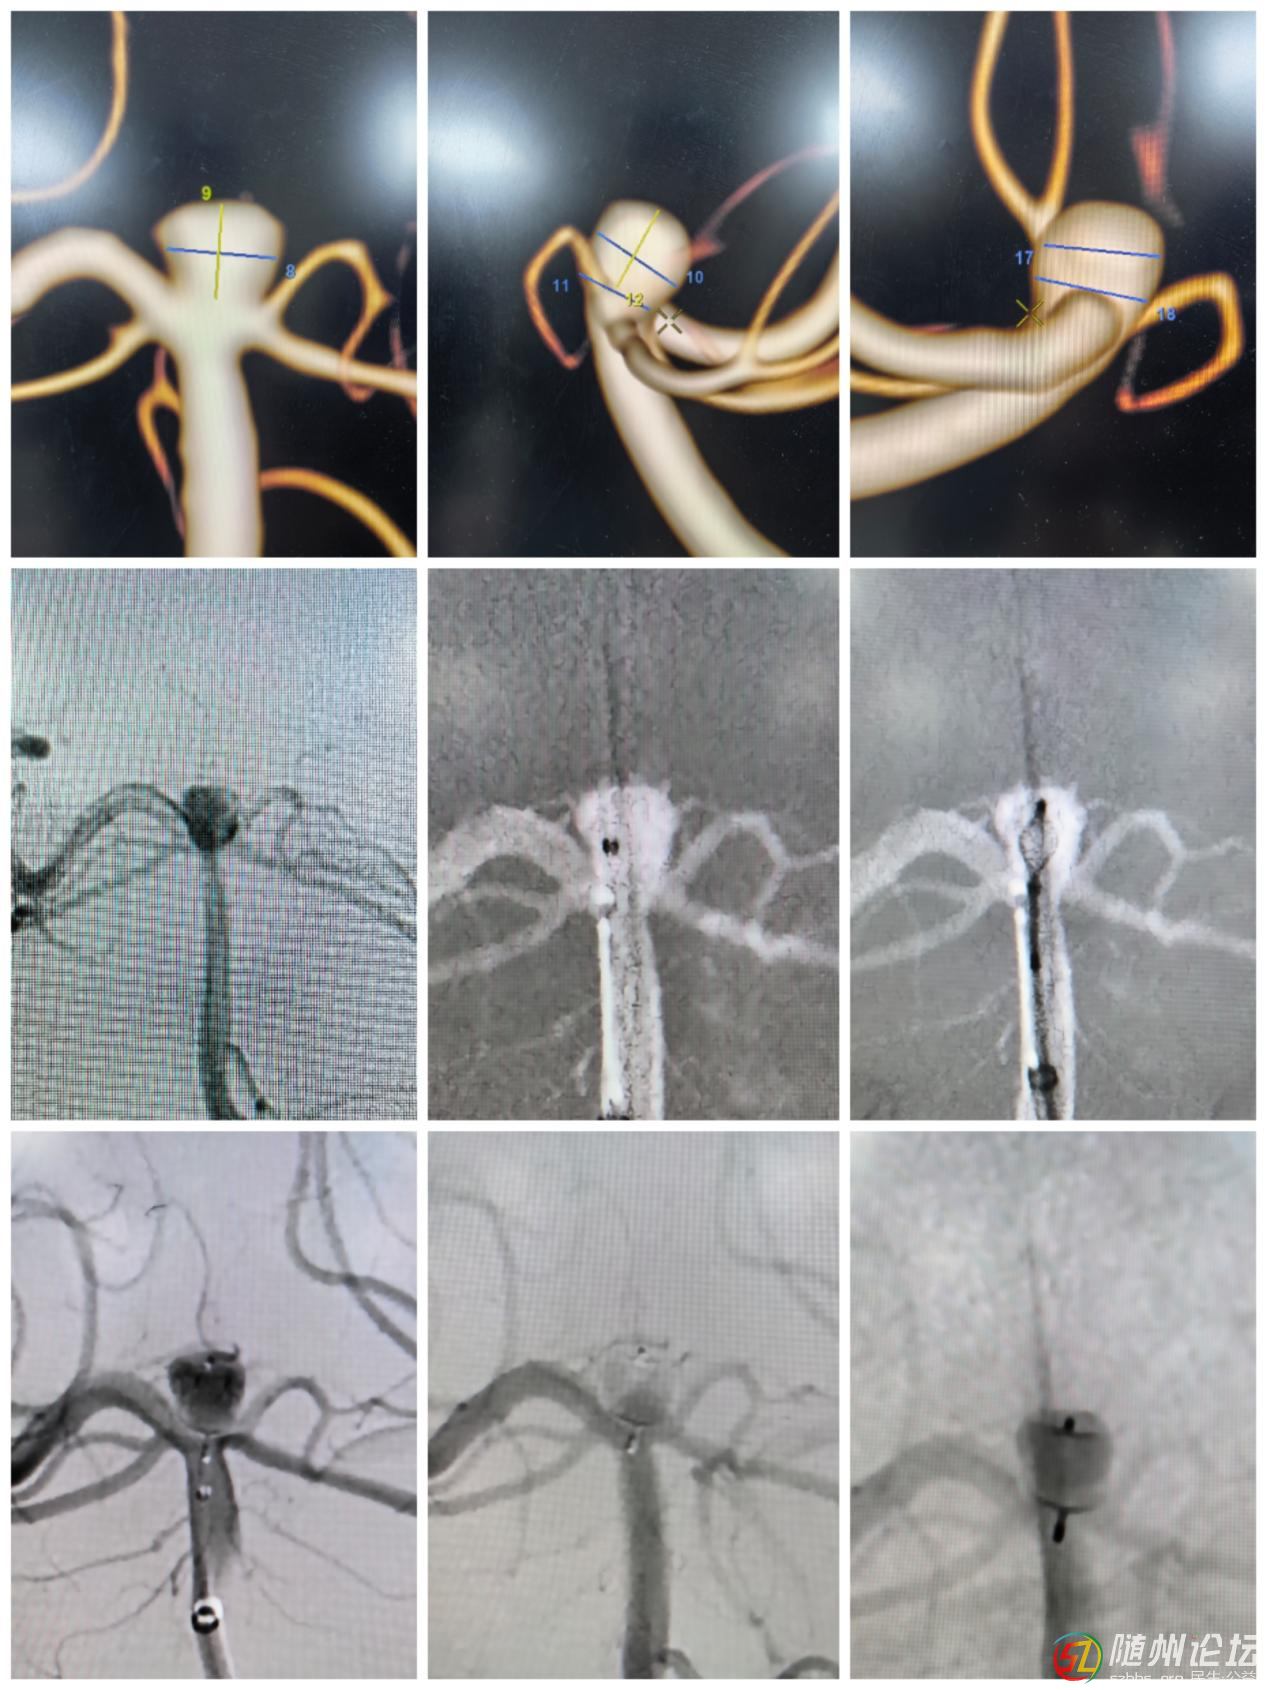

患者聶某(化名),66歲,一周前因頭暈、視物模糊就診,經(jīng)檢查發(fā)現(xiàn)基底動(dòng)脈尖分叉部有一寬頸動(dòng)脈瘤。該位置解剖結(jié)構(gòu)復(fù)雜,分支動(dòng)脈多,傳統(tǒng)栓塞手術(shù)風(fēng)險(xiǎn)高、難度大,難以致密填塞并保留全部分支動(dòng)脈。經(jīng)過(guò)多學(xué)科專家討論,團(tuán)隊(duì)決定采用國(guó)際先進(jìn)的WEB技術(shù)進(jìn)行精準(zhǔn)介入治療。

患者手術(shù)圖示

手術(shù)中,程偉主任醫(yī)師、黃豫軍副主任醫(yī)師通過(guò)介入方式將WEB裝置通過(guò)微導(dǎo)管置入動(dòng)脈瘤腔內(nèi),利用其自膨脹網(wǎng)狀結(jié)構(gòu)即刻阻斷血流,避免瘤體破裂風(fēng)險(xiǎn)。整個(gè)手術(shù)僅耗時(shí)約1小時(shí)余,術(shù)后聶先生恢復(fù)良好,無(wú)神經(jīng)功能損傷,72小時(shí)后順利出院。